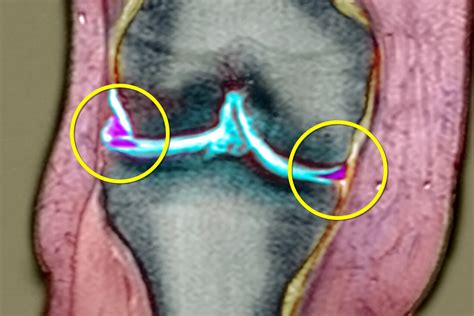

When looking at Torn Meniscus MRI pictures, the goal is to identify signal abnormalities within this cartilage structure. Healthy menisci appear as dark, triangular shapes on standard MRI sequences. When a tear is present, it disrupts this dark signal, allowing bright fluid or scar tissue to show up in the image.

Radiologists are trained to scrutinize the meniscus for specific patterns of signal intensity. A healthy meniscus should have low signal intensity (meaning it looks black on the MRI). A torn meniscus typically exhibits increased signal intensity (appearing white or bright) within the substance of the cartilage.

However, it is important to note that not all bright signals are tears. Sometimes, age-related degeneration can cause internal signal changes that do not actually represent a structural tear that requires surgery. A tear is definitively diagnosed when the high-signal intensity extends to the articular surface of the meniscus. When you see this on an MRI, it confirms that the cartilage has been compromised.

Types of Tears Visible on Imaging

Not all tears look the same on an MRI. The shape and location of the tear heavily influence treatment recommendations. Common patterns seen on imaging include:

• Bucket Handle Tear: A severe type of longitudinal tear where the torn part of the meniscus flips into the center of the joint, often causing the knee to lock.